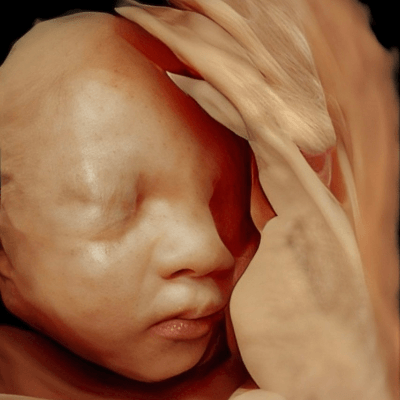

A woman underwent routine prenatal screening at 13 weeks. The non-invasive prenatal test (NIPT) showed low risk for common aneuploidies including trisomy 21, 18, and 13. However, first-trimester anomaly scan revealed multiple fetal anomalies.

Please describe the abnormalities and provide a syndromic diagnosis that best fits the presentation.